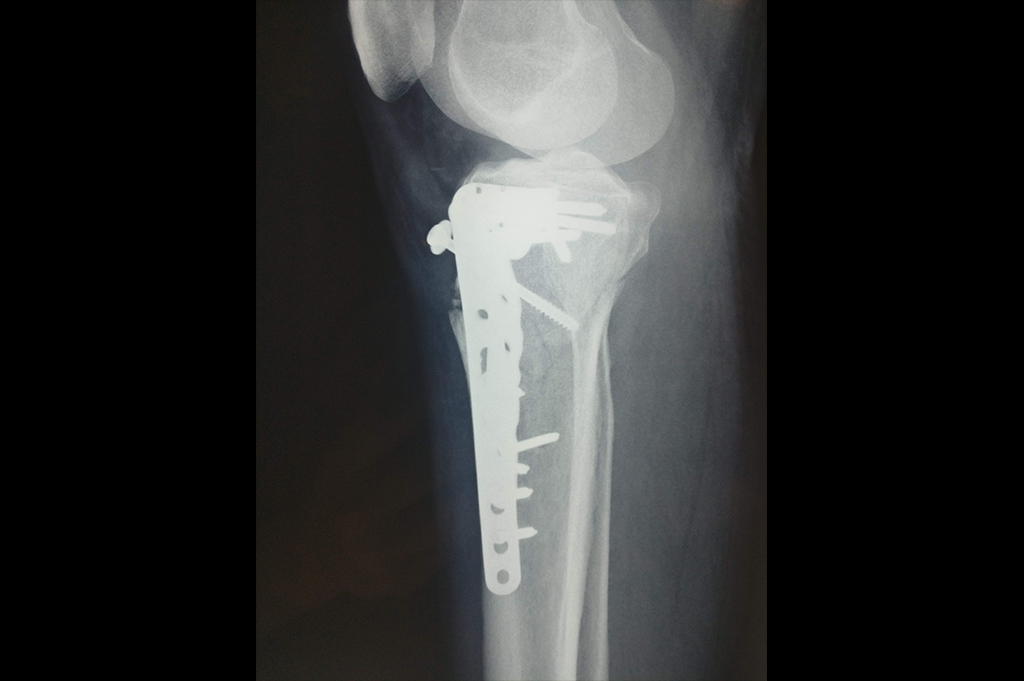

Osteoarthritis – High Tibial Osteotomy - HTO

Proximal Tibia